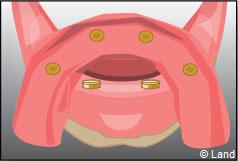

Les implants peuvent aussi servir à stabiliser un appareil amovible au maxillaire supérieur comme au maxillaire inférieur. Dans ce cas, les implants retiennent la prothèse amovible par des systèmes d’attachement.

Deux techniques sont possibles. Elles font appel à la barre de rétention ou aux boutons-pressions.